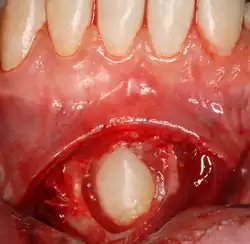

Pericoronitis

Pericoronitis is an infection of the soft tissue that covers the crown of an impacted tooth and is usually caused by the normal oral microbiota. For most people there exists a balance between the host defenses and the oral micriobiota but if the host defenses are compromised like during minor illness such as influenza or an upper respiratory tract infection, pericoronitis results. Another common cause is entrapment of food beneath the gum flap (also called an operculum). Pericoronitis can present as a mild infection or severe infection. In its mildest form it is just a localized tissue swelling and soreness whereas in severe forms the swelling is slightly larger even sometimes creating trismus (difficulty opening the mouth).

Sometimes, a surgeon may wish to expose the canine for aesthetic purposes. This may be achieved through open or closed exposure. Studies show no advantage of one method over another.[11] A laser can be used to uncover superficially impacted teeth with no bleeding and quick recovery.[12][13][14]